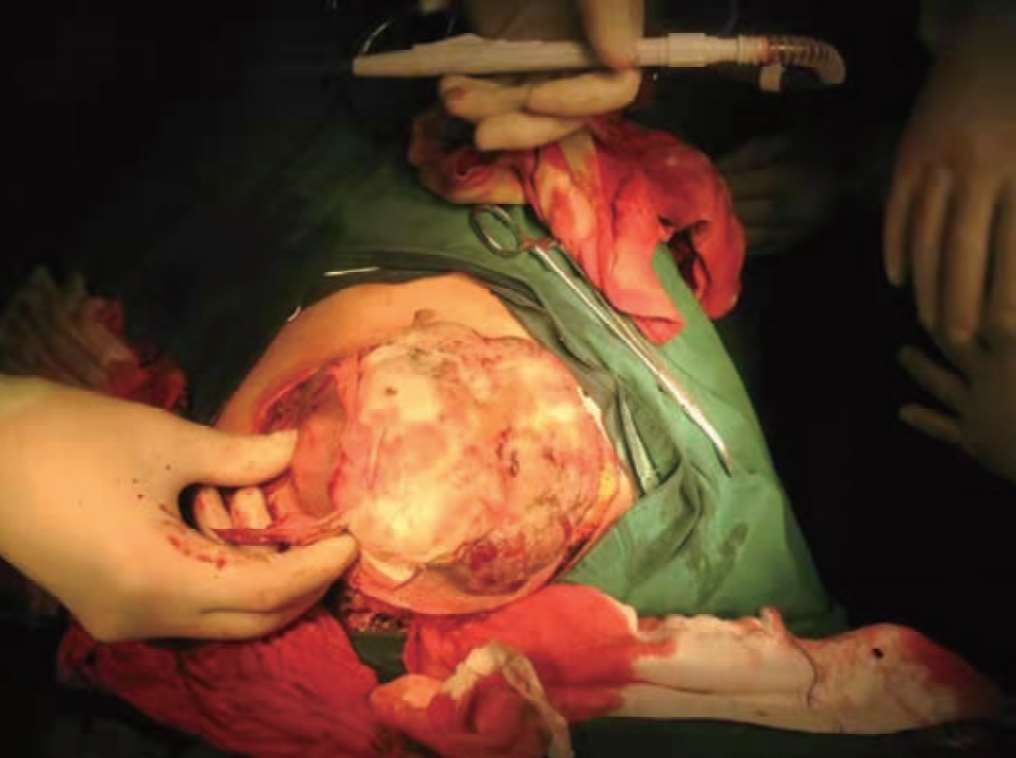

图2-8 术中切除肿瘤实况

说明:手术进行中的实况,术者认真、仔细地解剖、分离肿瘤。

图2-9 手术进行中

说明:手术进行中,术者同助手紧密协作,显露清除术野,认真解剖,在直视下仔细分离到逐步完整切除癌肿,尽可能保留正常组织的情景。

图2-10 正在切除肿瘤

说明:肿瘤即将被整块切除时的实况,在术者和助手的密切配合下,左侧乳房及巨大肿瘤被完整切除,左侧腋窝淋巴结也被清扫。充分游离剩余的正常组织皮下层,包括右侧乳房上腹壁以及左侧胸背部皮下软组织层后,利用这些组织做成带蒂的组织瓣,封闭前胸壁巨大缺损。术中首次使用右侧乳房内侧乳房及带蒂皮瓣修复左侧胸壁软组织的巨大缺损区,用钢丝减张缝合的办法拉拢皮肤与皮下组织切口两边,使切口两边缘的张力减小,最后用七号丝线缝合伤口,使前胸壁的巨大软组织缺损区得到修复。